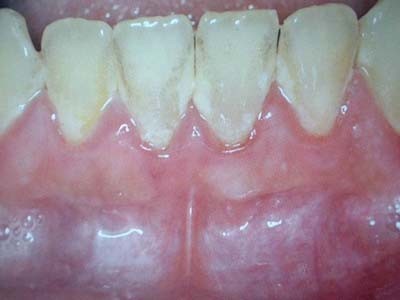

牙髓炎是指发生于牙髓组织的炎性病变。牙髓包含神经血管的疏松结缔组织,位于牙齿内部的牙髓腔内,因各种原因受到病源刺激物的影响可引起牙髓炎症,即牙髓炎,主要症状为疼痛,甚至是剧烈的难以忍受的疼痛,常会使患者坐卧不安,饮食难进,痛苦不堪

牙髓炎是比较常见的牙齿疾病,以疼痛为主要症状,主要分为急性牙髓炎和慢性牙髓炎。